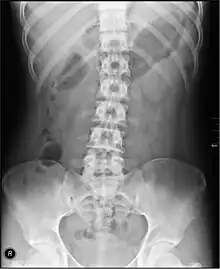

Une radiographie de l'abdomen sans préparation.

La radiographie de l'abdomen sans préparation, plus souvent abrégé « Abdomen sans préparation » (ASP) ou abdomen à blanc consiste à radiographier l'abdomen sans produit de contraste, contrairement au transit baryté ou au lavement baryté.